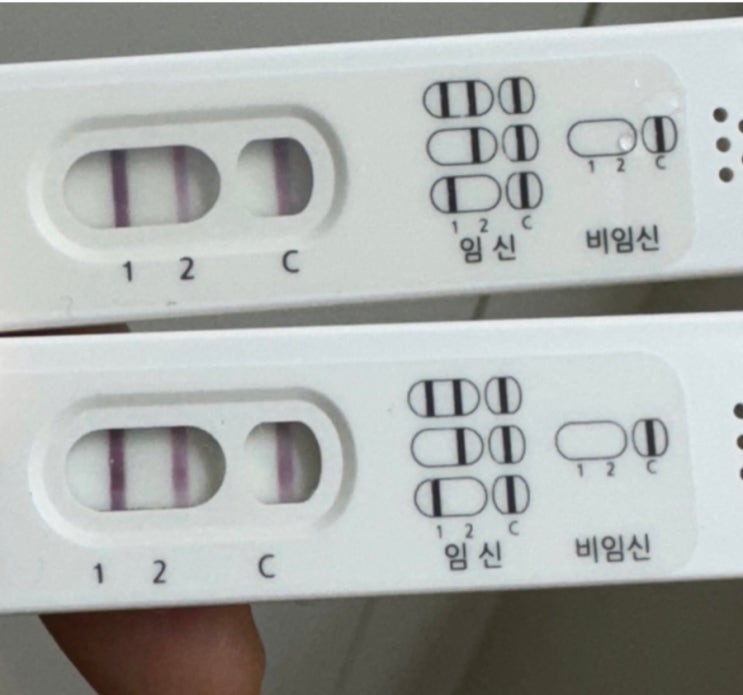

난포를 키우기 위해 페마라를 5일간 복용하고 배란초음파를 확인하러 병원을 방문했다. 다행히 난포도 잘 ...